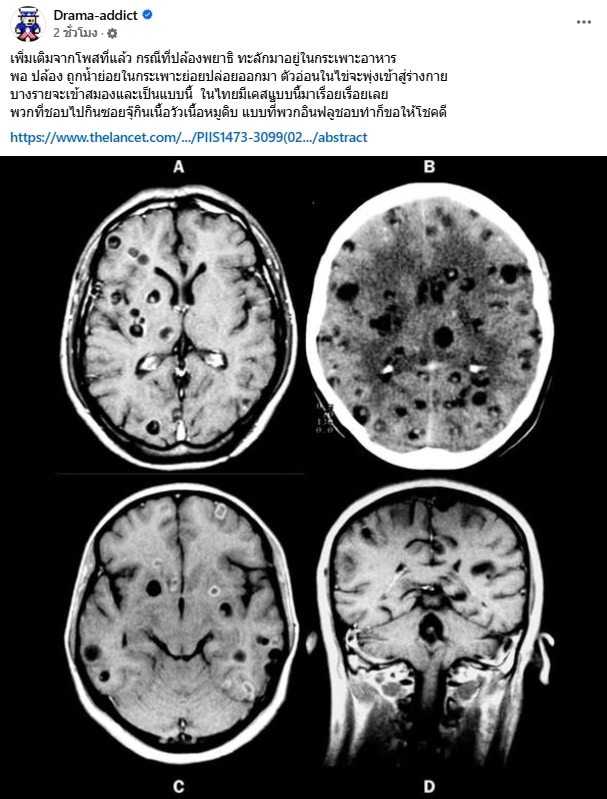

ล่าสุดเพจ Drama-addict ก็มีความเคลื่อนไหวถึงกรณีดังกล่าวด้วยเช่นกัน โดยโพสต์ภาพผลเอกซเรย์สมองของคนไข้รายหนึ่ง ซึ่งภาพที่ปรากฎให้เห็นคือ สมองคนที่มี พยาธิ ฝังกระจ่ายอยู่ทั่วสมอง พร้อมระบุข้อความเตือนภัยสาวกซอยจุ๊ ระบุว่า

“กรณีที่ปล้องพยาธิ ทะลักมาอยู่ในกระเพาะอาหารพอ ปล้อง ถูกน้ำย่อยในกระเพาะย่อยปล่อยออกมา ตัวอ่อนในไข่จะพุ่งเข้าสู่ร่างกาย บางรายจะเข้าสมองและเป็นแบบนี้ ในไทยมีเคสแบบนี้มาเรื่อยเรื่อยเลย พวกที่ชอบไปกินซอยจุ๊กินเนื้อวัวเนื้อหมูดิบ แบบที่พวกอินฟลูชอบทำก็ขอให้โชคดี”

อีกทั้งก่อนหน้านี้ Drama-addict ได้แชร์โพสต์ของหมอแล็บแพนด้า พร้อมระบุข้อความให้ความรู้เพิ่มเติมว่า “ปกติพยาธิตัวตืดมันจะอยู่ในลำไส้ยกเว้นบางทีที่ปริมาณเยอะมากๆจนล้นทะลักออกมาแบบนี้ ซึ่งความน่ากลัวนั้นไม่ใช่แค่ในคลิปที่เห็น แต่เมื่อปล้องของพยาธิตัวตืด ทะลักมาอยู่ในกระเพาะอาหาร และเจอกับน้ำย่อยในกระเพาะ มันจะย่อยปล้องและปล่อยไข่จำนวนมหาศาลออกมานับ 100,000 นับ 1,000,000 ฟอง ไข่พวกนั้นจะกลายเป็นตัวอ่อนชอนไชเข้ากระเพาะและทะลุทะลวงไปสู่อวัยวะต่างๆทั่วร่างกาย บางตัวก็ขึ้นตาขึ้นสมอง ความสยองของจริงจะเริ่มขึ้นตอนนั้น“